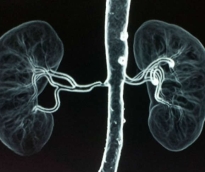

بات من غير المرجح أن يشهد المرضى الذين عولجوا باستئصال عصب في الشريان الكلوي هبوطا في ضغط الدم، مقارنة بأولئك الذين تلقوا علاجا مموها في تجربة إكلينيكية كبرى. وألقى ذلك بظلاله على علاج تطبقه أكثر من 80 دولة في الحالات المستعصية من ارتفاع الضغط التي لا تستجيب للعقاقير. وتمثل هذه الدراسة اختبارا حاسما للتدخل الجراحي الذي يتضمن قطع الموصلات العصبية بين القلب والكلى في محاولة لخفض ضغط الدم لأن التجارب السابقة لم تكن تتضمن مجموعة مقارنة لحسم فاعلية الجراحة. ولم تشتمل التجارب السابقة على تقنية إعطاء بعض المرضى علاجا مموها على سبيل المقارنة يمكنه ان يعطي صورة جلية عن التباين في مستوى ضغط الدم. ويعتزم الباحثون متابعة حالات المرضى خمس سنوات قادمة لرصد أي فوائد متأخرة قد تتحقق خلال مرحلة المتابعة.

أكدت دراسة ألمانية، أن ارتفاع ضغط الدم وأمراض الكُلى وجهان لعملة واحدة؛ حيث يُلحق ارتفاع الضغط تلفيات بالكُلى تتسبب في فقدانها القدرة على تأدية وظيفتها. ومن ناحية أخرى، يترتب على تدهور وظيفة الكُلى تزايد الهرمونات التي تتسبب في ارتفاع ضغط الدم. كما يؤدي تراجع إفرازات البول الناجم عن تدهور وظيفة الكُلى إلى تزايد كمية الماء المحتبسة بالجسم، ما يؤدي بدوره إلى ارتفاع ضغط الدم. وأشارت الرابطة الألمانية لأطباء أمراض الباطنة، إلى أن تلفيات الكُلى تعد ثالث أسباب الوفاة شيوعاً لدى مرضى ارتفاع ضغط الدم، مؤكدة أن الفحص الدوري للكُلى يساعد على اكتشاف أية أمراض بها، مثل الفشل الكلوي، مبكراً ومن ثم علاجها جيداً. لذا ينبغي على مرضى ارتفاع ضغط الدم إجراء فحص للبول مرة كل سنة للتأكد من سلامة الكُلى لديهم. ولتجنب الإصابة بارتفاع ضغط الدم من الأساس، أوصت الرابطة الألمانية بإتباع أسلوب حياة صحي يقوم على ممارسة الرياضة والأنشطة الحركية والتغذية السليمة التي ترتكز على الإكثار من الخضروات والفواكه والإقلال من الدهون والملح.